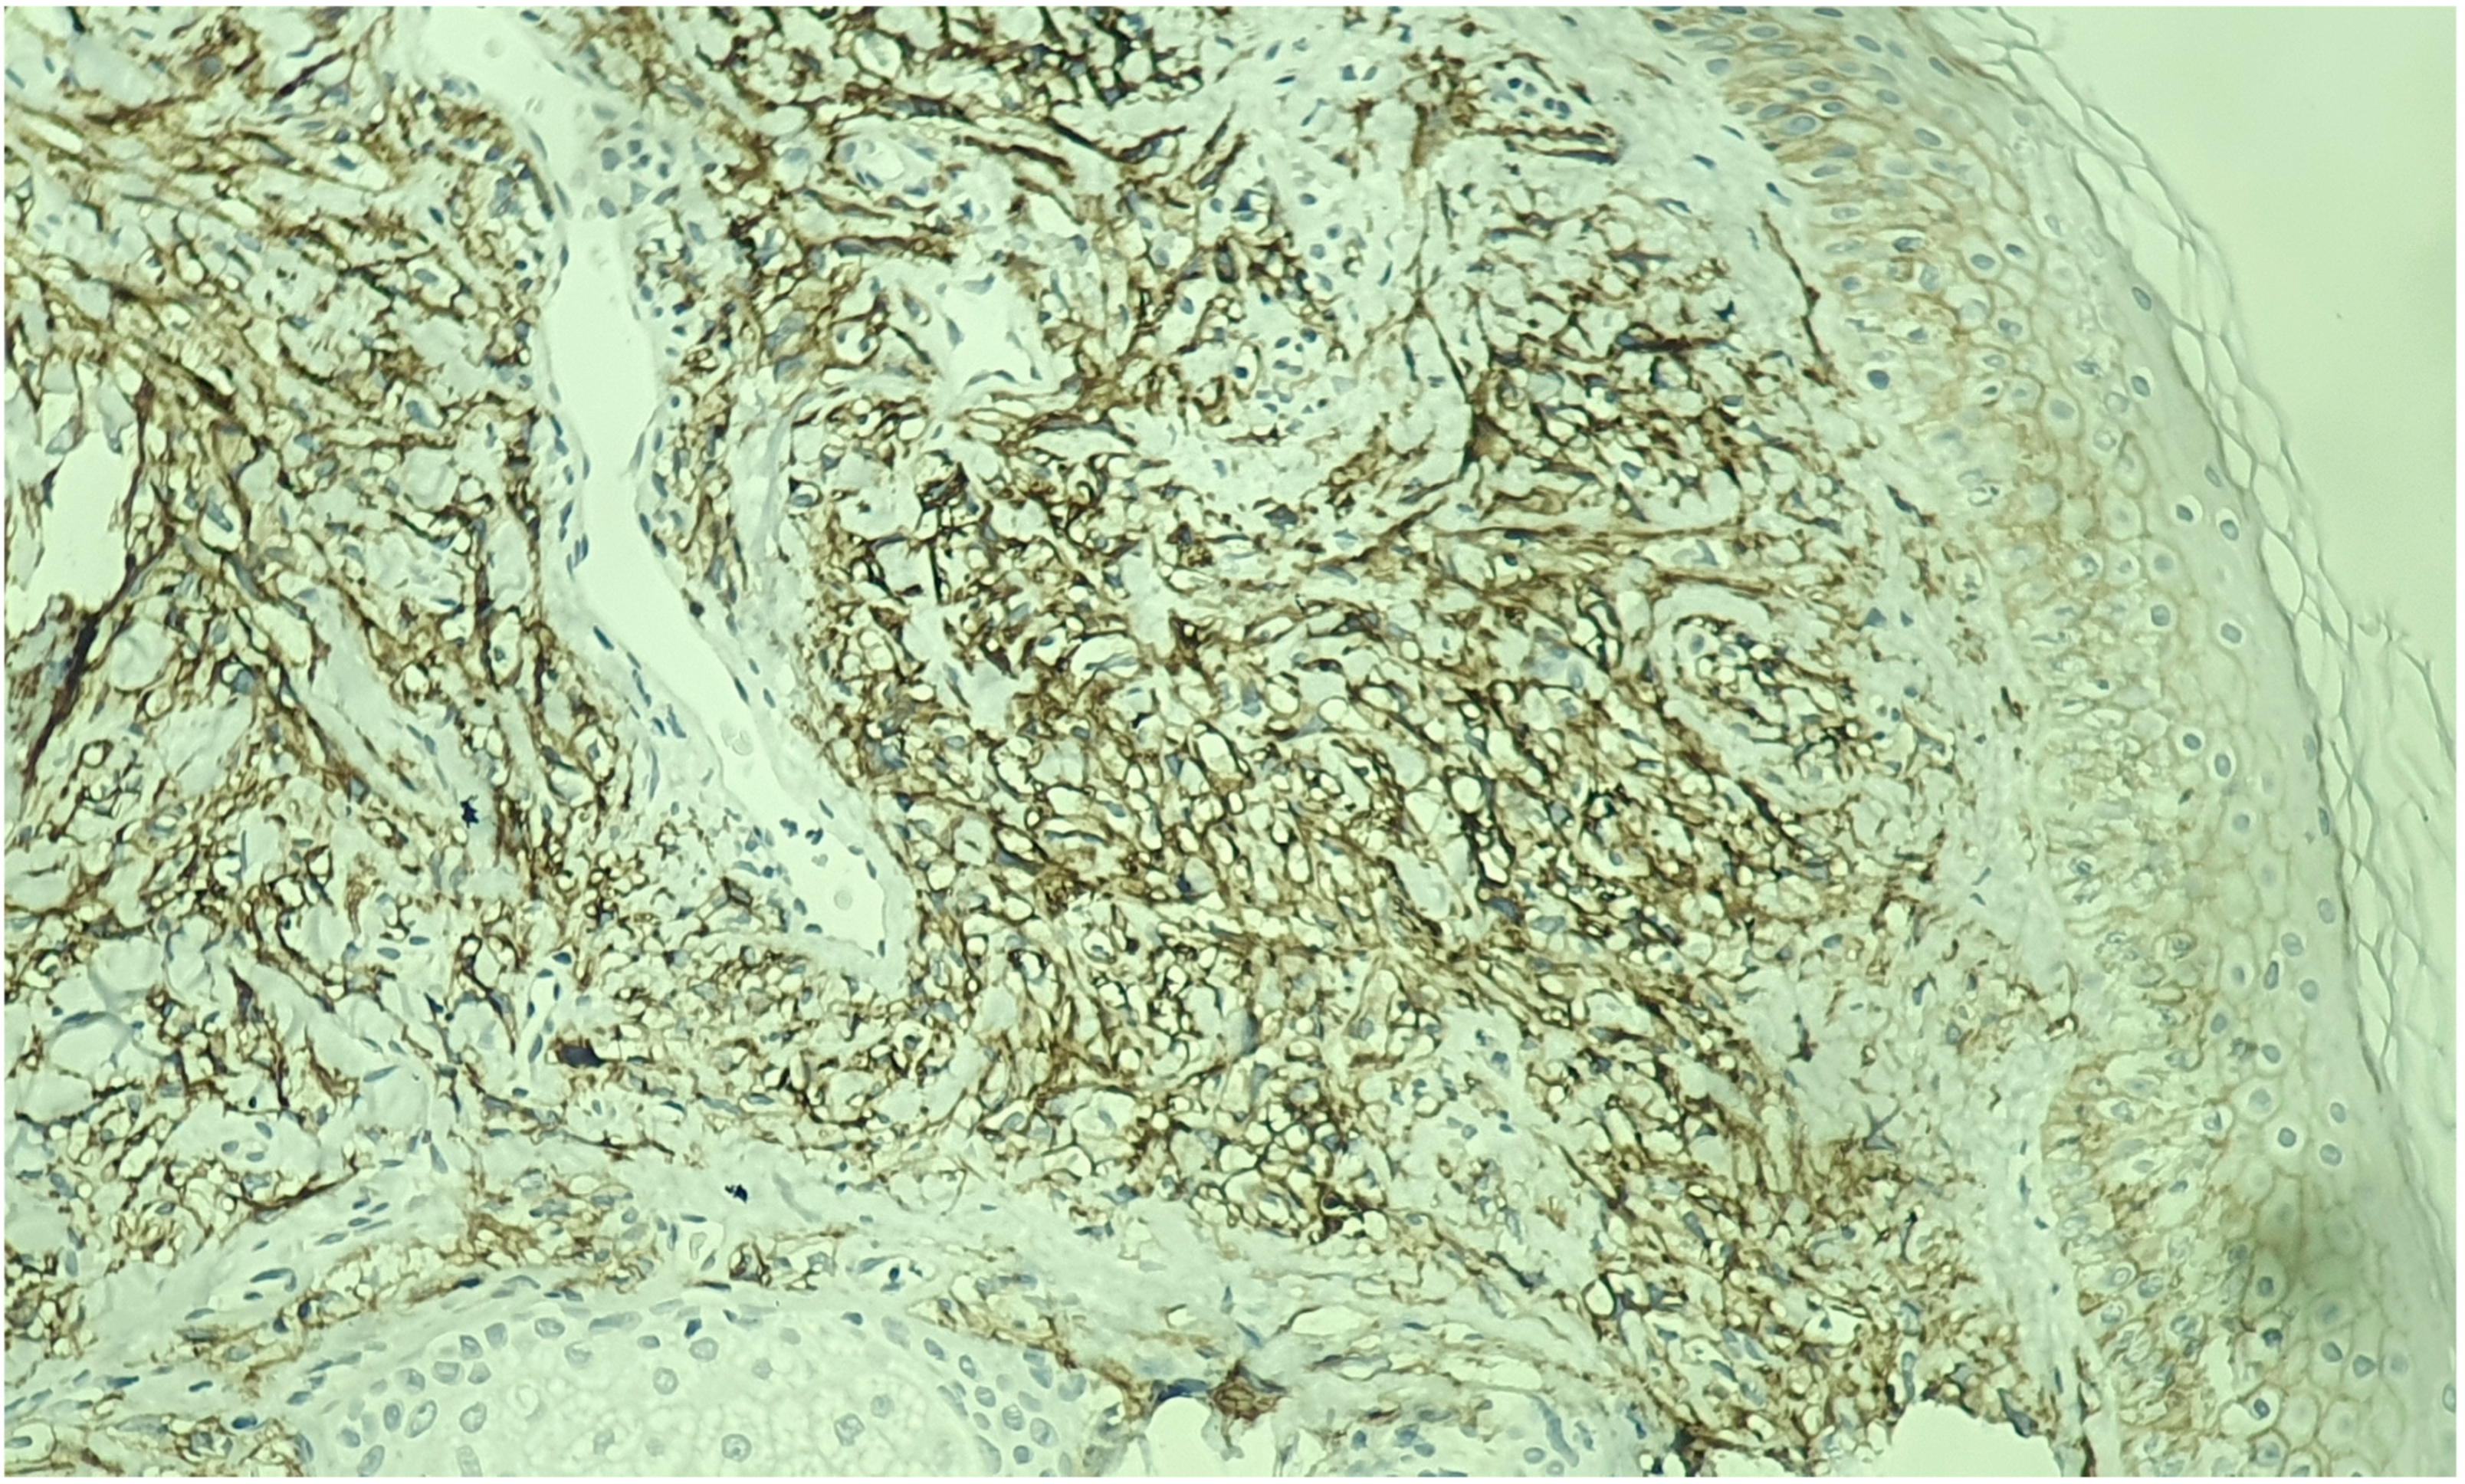

2. Case Report